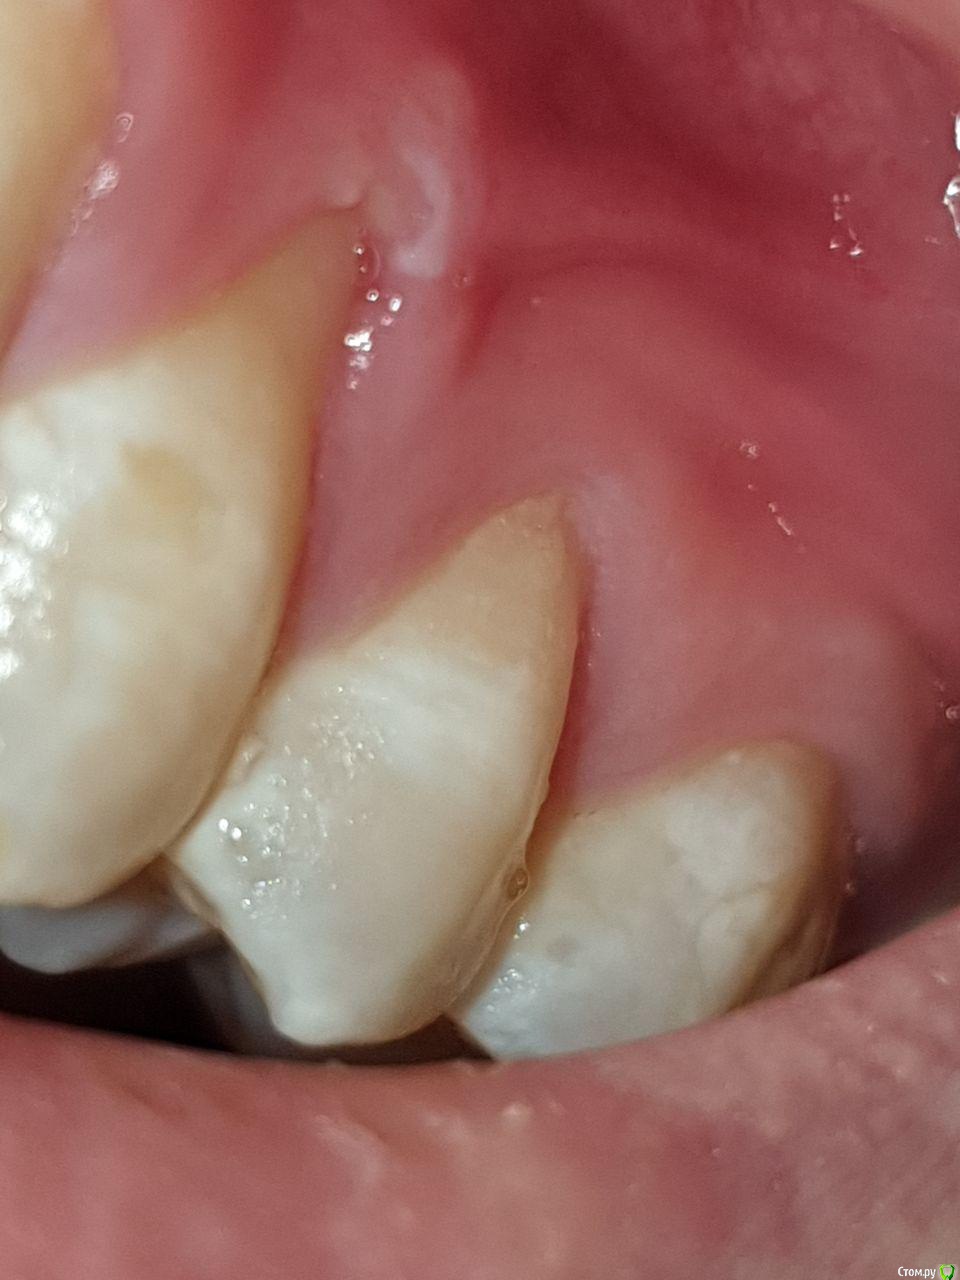

Сразу после того как выздоровел началась проблема - на 4ом зубе слева начала задираться десна. Затем со временем и на правом 4ом зубе тоже

Стал фиксировать убыль на фотографиях, которые приложу к данному посту. Также прикладываю результаты анализов. Помимо этого полгода назад делали панорамный снимок, который вроде как показал, что убыли костной ткани нет. На вопрос а в чем тогда проблема, мне ответили, что это просто рецессия (видимо, так задумано и все ок, пока зуб не выпадет подождем).

Добрый день. То что происходит - это рецессия десны. Десна "уползает" от коронки зуба у всех, вопрос скорости и равномерности. В вашем случае и возрасте это быстрее чем в норме.